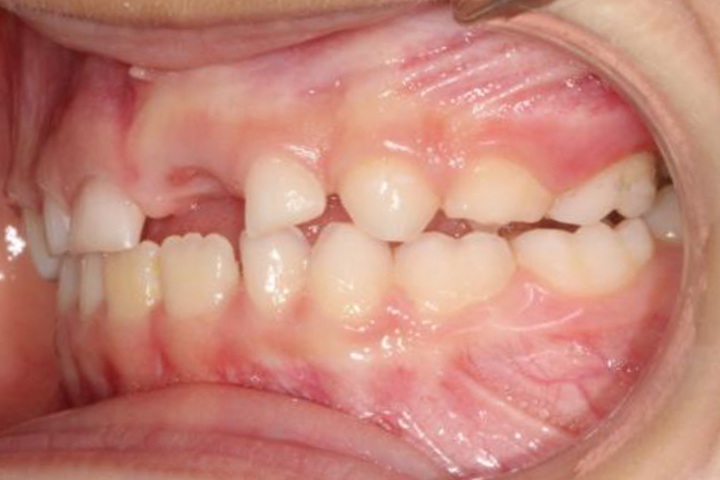

Maddy è una bimba di 5 anni che si presenta con una terza classe dento-scheletrica (indice di wits – 7 mm).

È stata trattata per 10 mesi con espansione ortodontica (leaf expander) e maschera di Petit, correggendo la malocclusione durante l’ultima fase della dentatura decidua.